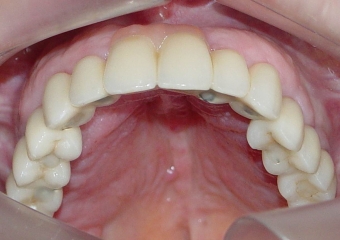

Imagens da prótese fixa superior em porcelana sobre implantes Cone Morse